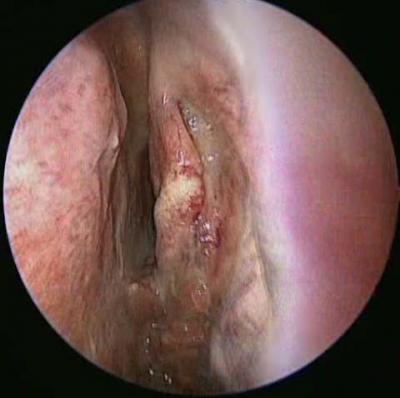

Figure 1: Endoscopic picture of the left nasal cavity which shows a polypoidal fleshy mass (double arrows) arising from the middle meatus and extending into the nasopharyx (single arrow pointing to the middle tur- binate).